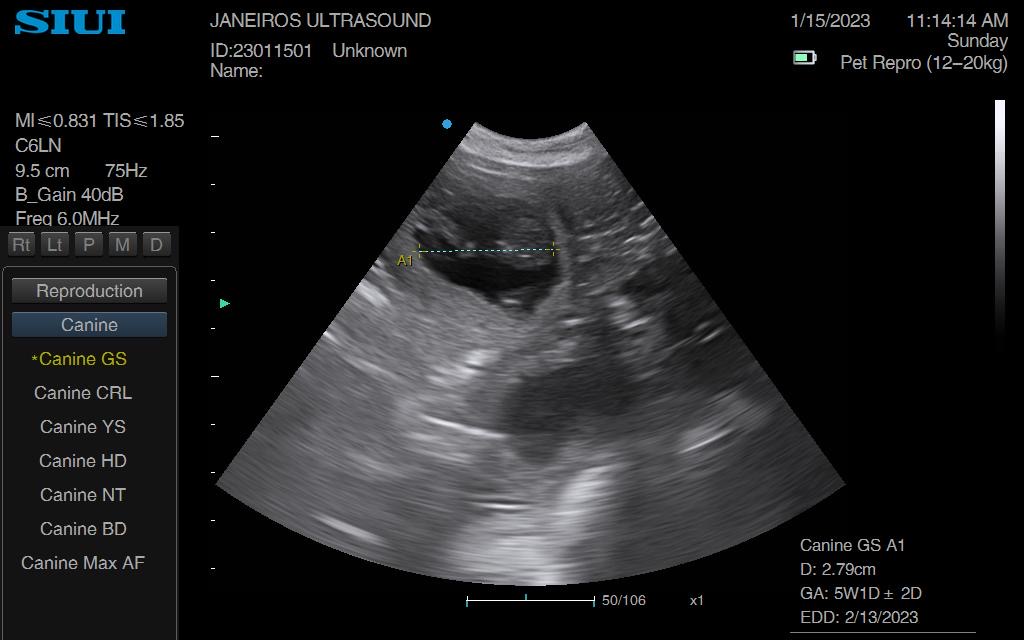

Spring forward to today. Measurements taken suggested 5wks and 1 day gestation and 6 sacs!!

Confirmed heartbeats on each puppy. All cooking away nicely.

The pictures and videos are so much clearer at this stage. Trust me.. don’t fib to you scanner regarding dates, it’s really not worth it! 😊